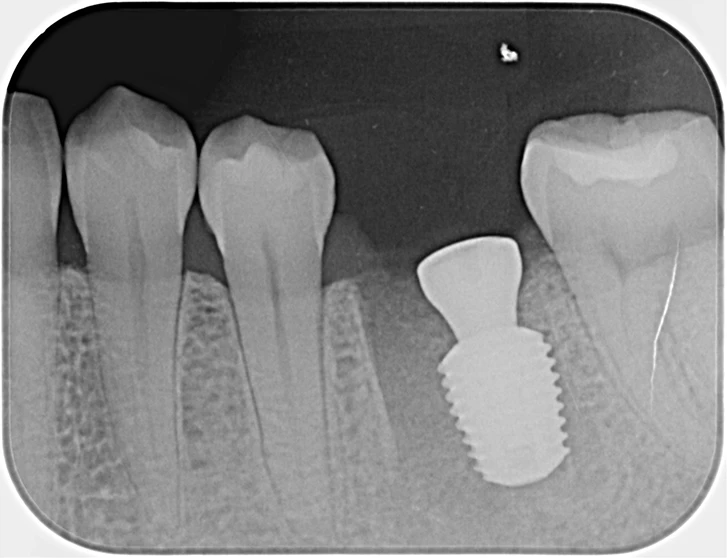

40代、女性、左下噛むと痛いこと主訴に来院され、インプラント治療を行いました。

| 診断結果 | 左下6番歯根破折 |

| 治療内容 | 抜歯即時インプラント |

| 治療期間 | 8週間 |